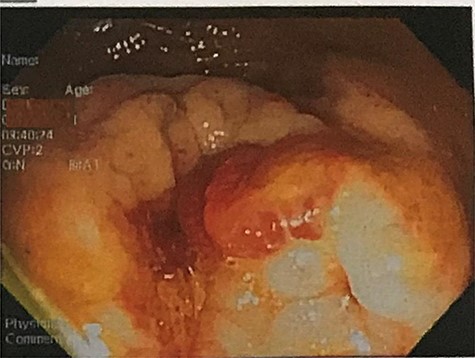

A 32-year-old man with no past medical or surgical history presented to the emergency department (ED) in April 2018, distressed and complaining of worsening pneumaturia for the past 3 days. The patient reported a 2-week history of polyuria, dysuria, suprapubic pain, tenesmus and inability to control his sphincters, prior to the ED-onset presentation. Further history revealed a 50-pound involuntary weight loss in a 5-month period, with partially treated urinary tract infections without resolution. He denied toxic habits, high-risk sexual behavior nor family history for colorectal cancer or inflammatory bowel disease. Based on the symptoms described, the rare triad of Gouverneur’s syndrome related to the EVF was considered. Physical evaluation revealed no palpable anorectal masses, adequate rectal tone and no visible gross blood. Urine analysis showed pyuria, hematuria, proteinuria with urine culture positive for Escherichia coli. Abdominopelvic computed tomography (CT) scan showed circumferential wall thickening of the rectum with surrounding fat stranding and numerous prominent pelvic lymph nodes (Fig. 1). Additionally, the scan showed pericolonic gas and fluid collection with a fistulous tract adjacent to the proximal rectum and the bladder (Fig. 2). In Figure 3, two hepatic hypodense lesions located in the right lobe of the liver were identified suggestive of metastasis. During colonoscopy, at approximately 20 cm from the anal verge a large, firm, irregular, friable, concentric mass was identified obstructing 95% of the lumen (Fig. 4). During surgery, the mass was not amenable for resection, due to its low pelvic location and size; a loop colostomy was performed for decompression, with liver tru-cut needle biopsy. Intraoperative cystoscopy was unsuccessful in placement of ureteral stents due to tumor invasion to the bladder.

Colonoscopy results showing a large, irregular, friable concentric lesion occluding 95% of the lumen, 20 cm from the anal verge.